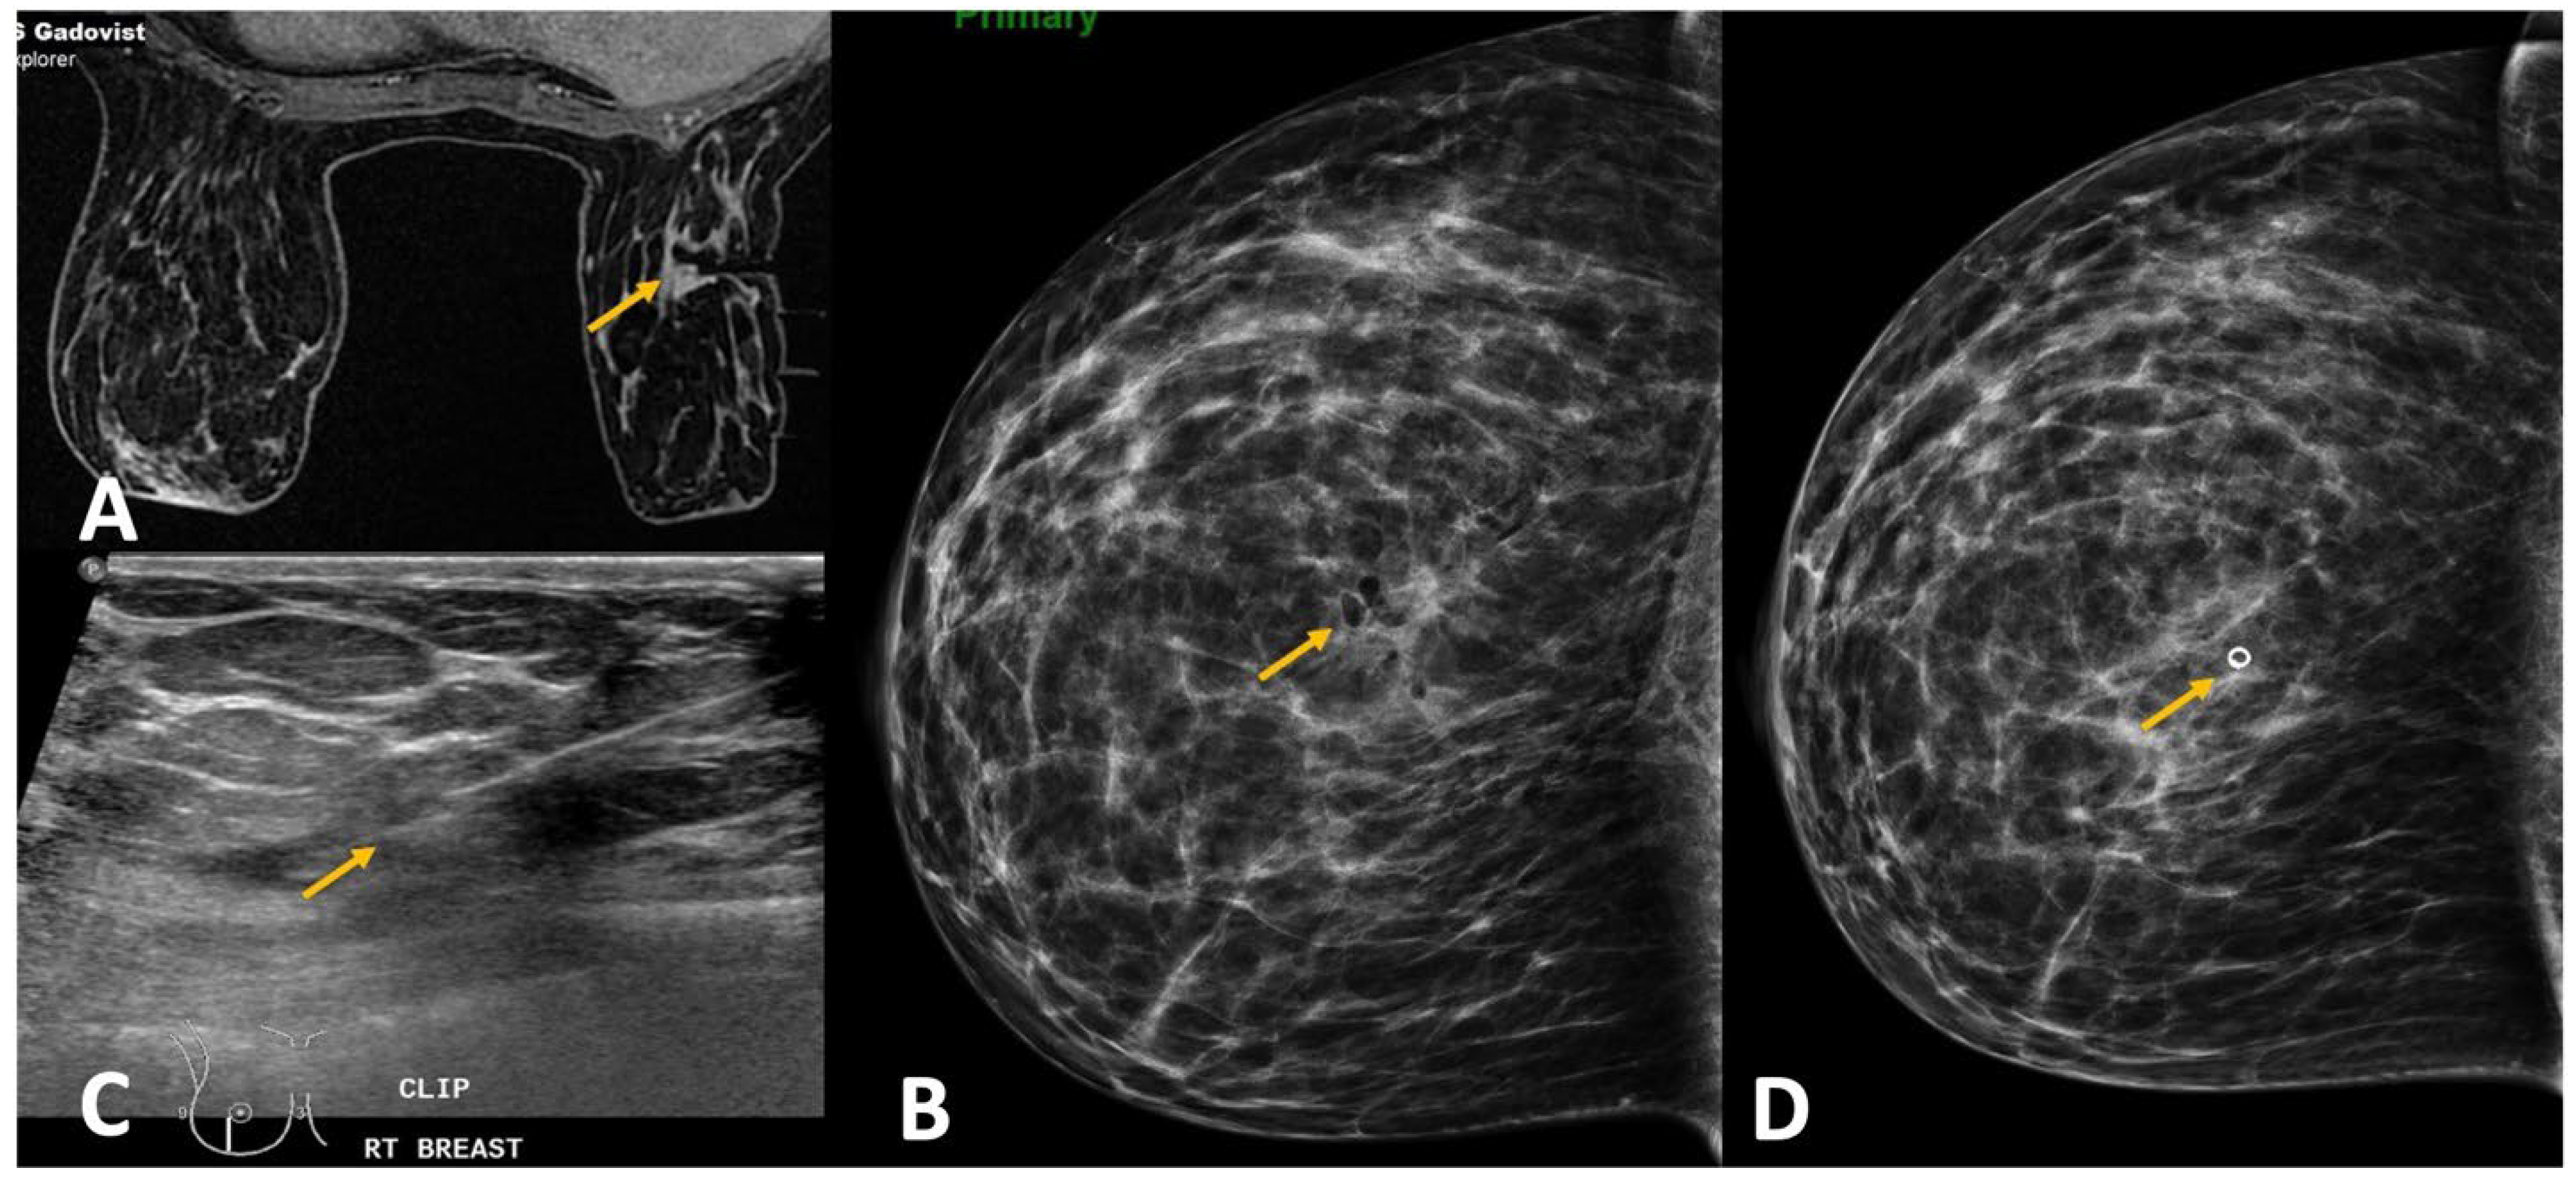

Figure 3.

(A). MRI was performed in a woman with architectural distortion on mammogram detected during screening without sonographic correlate. A small enhancing correlate was identified on MRI (yellow arrow). (B). The breast size was extremely small. After removing the padding from the breast coil, the patient was tilted to obtain the target site in the grid hole. Additional padding was applied on the medial aspect (white arrows) to obtain optimal breast thickness making the procedure feasible and the target lesion (yellow arrow) accessible. (C). Tip of the obturator was noted at the target site (yellow arrow) and biopsy was performed using blunt tip Petit needle. (D). Post-biopsy hematoma (yellow arrow) is noted with adequate sampling. Histology was reported as radial scar.